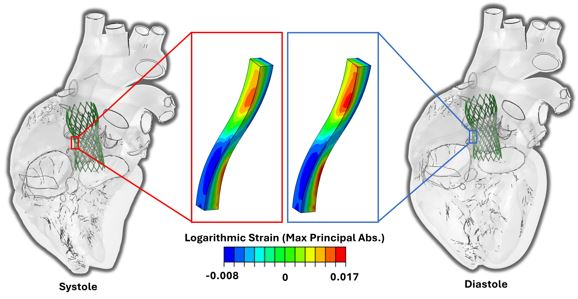

- Expansion of TAVR makes fatigue life and durability crucial to device success

- Nitinol stents experience cyclic displacements/strains in vivo, yet benchtop stent frame fatigue testing excludes beating heart effects and dynamic loading

- In silico approaches include beating heart effects, more accurate modeling of TAVR device durability

- The electro-mechanical SIMULIA Living Heart Human Model of a beating heart allows for virtually deploying devices to analyze displacements, associated strains, tissue stresses and contact forces

- With this approach, we examined TAVR stent design implications on fatigue outcomes by scaling strut width by 20%

- The primary cause of element failure was strain amplitudes exceeding fatigue limits for nitinol, where the failure threshold was overlaid on fatigue plots to analyze stent elements for each model that had "failed" virtually

![]()

- Our PolyV-2 stent demonstrated superior fatigue resistance when compared to the comemrcial CoreValve and Evolut R stents models, as it was previously optimized to minimize stresses and strains

- Localized modes of stent failure highlighted here in current commercial devices demonstrates the utility of intricate in silico models to evaluate stent design for optimization of fatigue resistance